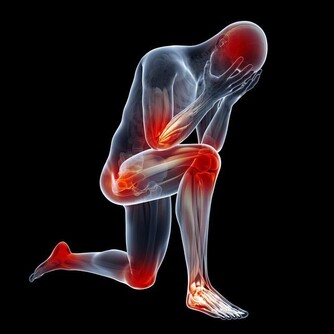

不同的情緒對應著不同的身體疾病。比如恐懼、焦慮會導致腹部疼痛;批評、內疚引發關節炎;

壓抑導致哮喘;經常憤怒的人容易有口臭,還愛發生膿腫;恐懼會引發暈車和痛經。